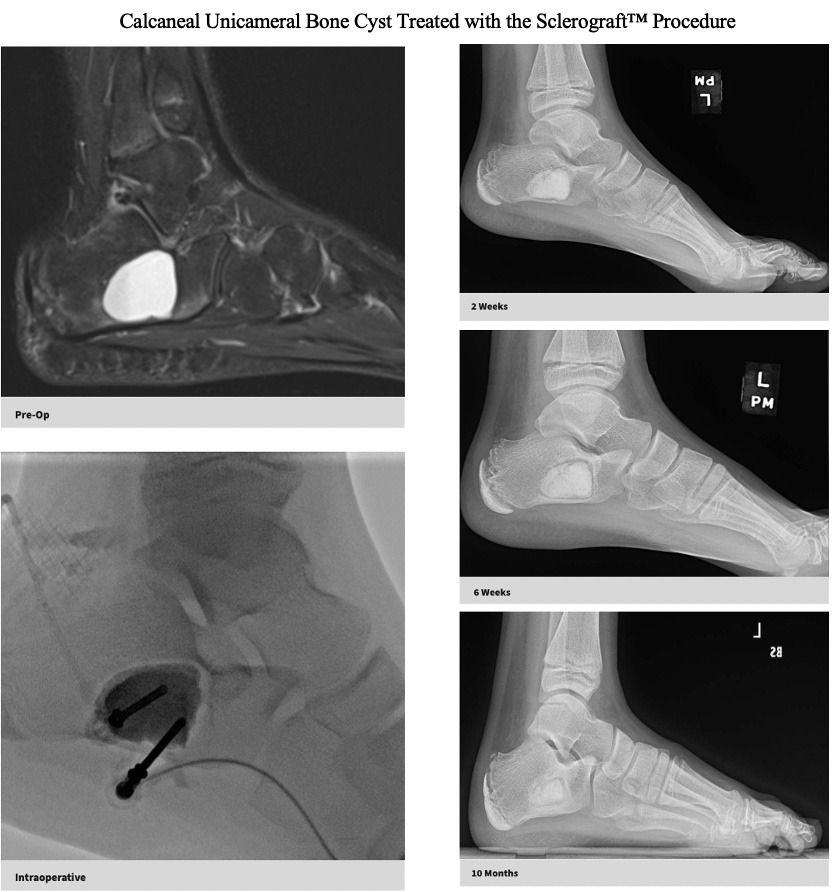

The Sclerograft procedure is a minimally invasive outpatient procedure used to treat bone cysts.

Utilizing needles, chemical sclerosis destroys the cyst wall and regenerative bone graft is injected via the needles to expedite bone healing.

The doctor uses imaging guidance (like X-ray or ultrasound) to guide needles into the cyst.

Chemical sclerosis using chemicals like doxycycline are washed through the cyst to kill the cyst wall lining

Regenerative bone graft is then injected through the needles and the needles are removed. The bone graft is temporary and is eventually reabsorbed by the body.

Quick recovery and bone formation seen between 6 weeks to 3 months

Gallery

Explore our educational resources and images